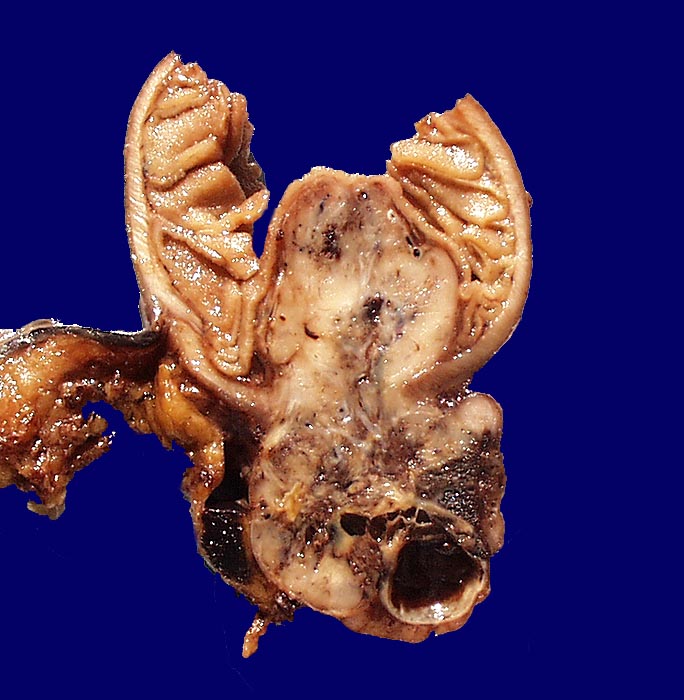

Makroskopisch imponieren kleine Tumoren als peritoneale, intramurale oder submuköse Knoten. Grössere Tumoren wölben sich oft vor und können ulzerieren. Die Schnittfläche ist weisslich und kann Einblutungen, Zysten, Fibroseareale oder Nekrosen aufweisen. Histologisch werden Spindelzelltyp (70%), Epitheloidzelltyp (20%) oder gemischtzelliger Typ (10%) unterschieden. Der histologische Subtyp scheint keinen Zusammenhang mit zugrundeliegender Mutation, Therapieansprechen und Prognose zu haben. Gelegentlich sind vor allem die kleineren Tumoren zellarm und kollagenreich.

• Scharf begrenzter kugeliger Tumor in der Submukosa des Magenantrums

• Über dem Tumor entzündungsfreie Antrumschleimhaut mit partiell reepithelialisiertem oberflächlichem Ulkus (Quellungsfibrinoid).

• Herdförmig pseudozystische Auflockerung des Tumorgewebes.

• Risikostratifikation nach Miettinen und Lasota (2006): Very low risk (sehr niedriges Risiko für Metastasen oder tumorbedingte Mortalität): Lokalisation im Magen, Grösse 22mm, fehlende Mitosen.